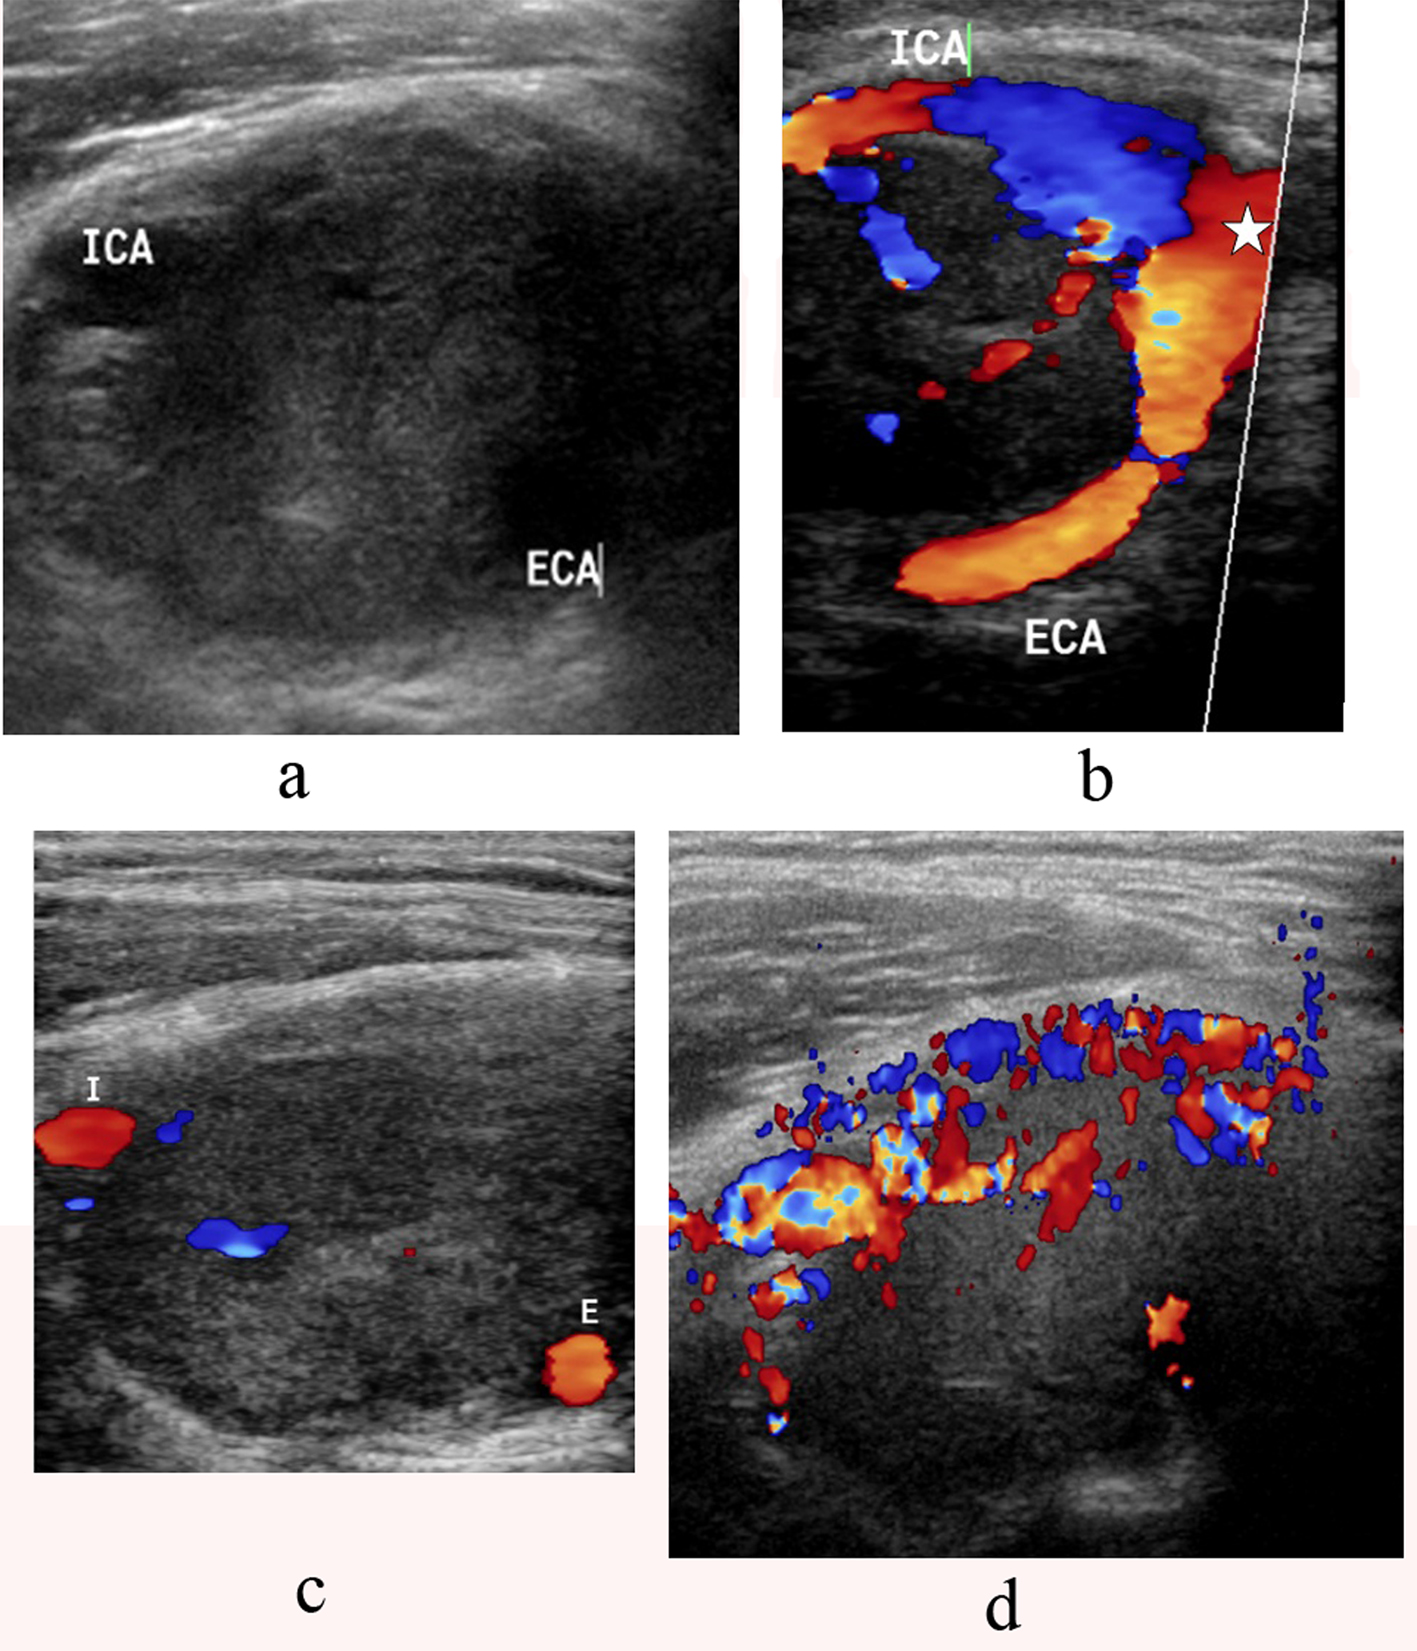

B-mode sonography showed a solid, well-defined, and hypoechoic tumor splaying the ICA and ECA (Fig. 2a). Color flow Doppler sonography showed also splaying of the internal and external carotid arteries by the mass with intratumoral vascularity (Fig. 2b-d).

![]() Click for large image | Figure 2. a-d. B-mode sonography showing a solid, well-defined, and hypoechoic tumor splaying the internal carotid artery(ICA) and external carotid artery (ECA) (a). Color flow Doppler sonography demonstrates a large mass at the carotid bifurcation. There is splaying of the internal carotid artery (ICA) and the external carotid artery (ECA) starting from the level of the common carotid bifurcation(star) (b, c) with high vascularity (d). |